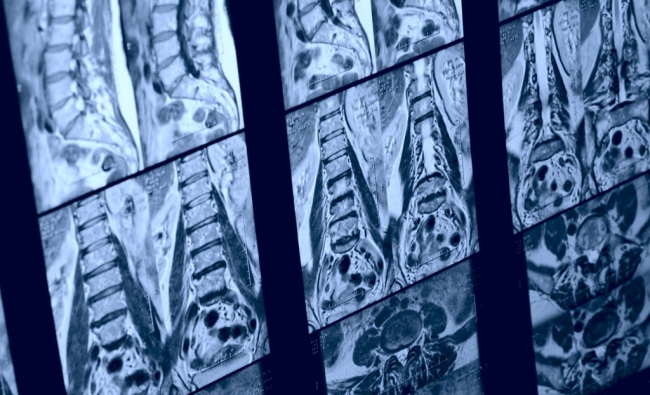

Tras el diagnóstico médico, cada vez son más los fisioterapeutas que emplean la ecografía como herramienta de evaluación del sistema músculo-esquelético permitiéndoles diseñar la mejor estrategia terapéutica. Sin embargo, no todas las lesiones son evaluables ecográficamente o la ecografía no es precisamente la mejor de las técnicas, bien por los artefactos que genera o por el periodo temporal en el que se encuentra la lesión.

Por este motivo, consideramos que, sin invadir competencias diagnósticas con el facultativo médico, en este curso teórico sería interesante que el fisioterapeuta conociera también el resto de técnicas de imagen que son capaces de evaluar el sistema músculo-esquelético, identificando su pertinencia, indicaciones y contraindicaciones.